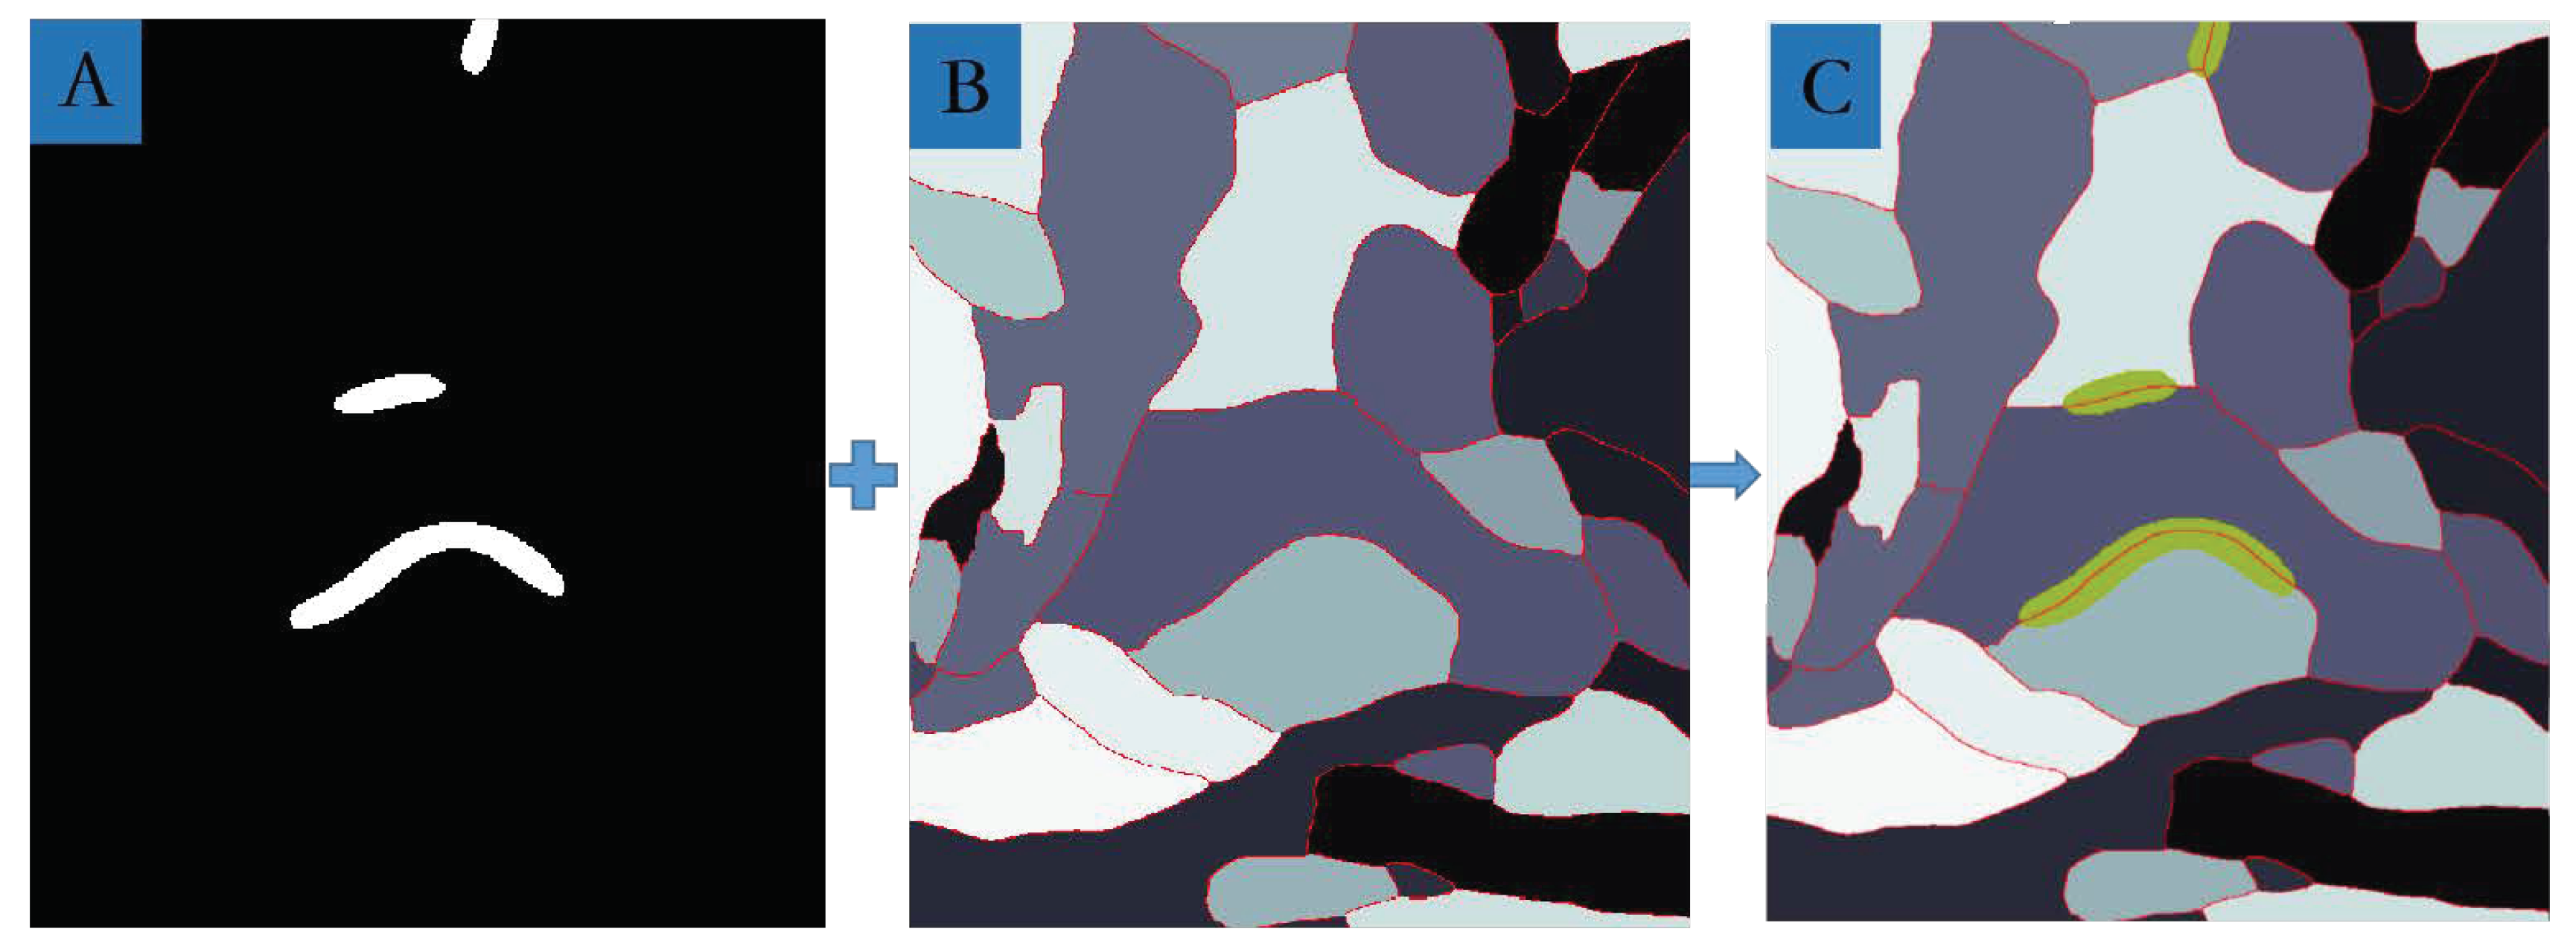

3.4. MSB Identification